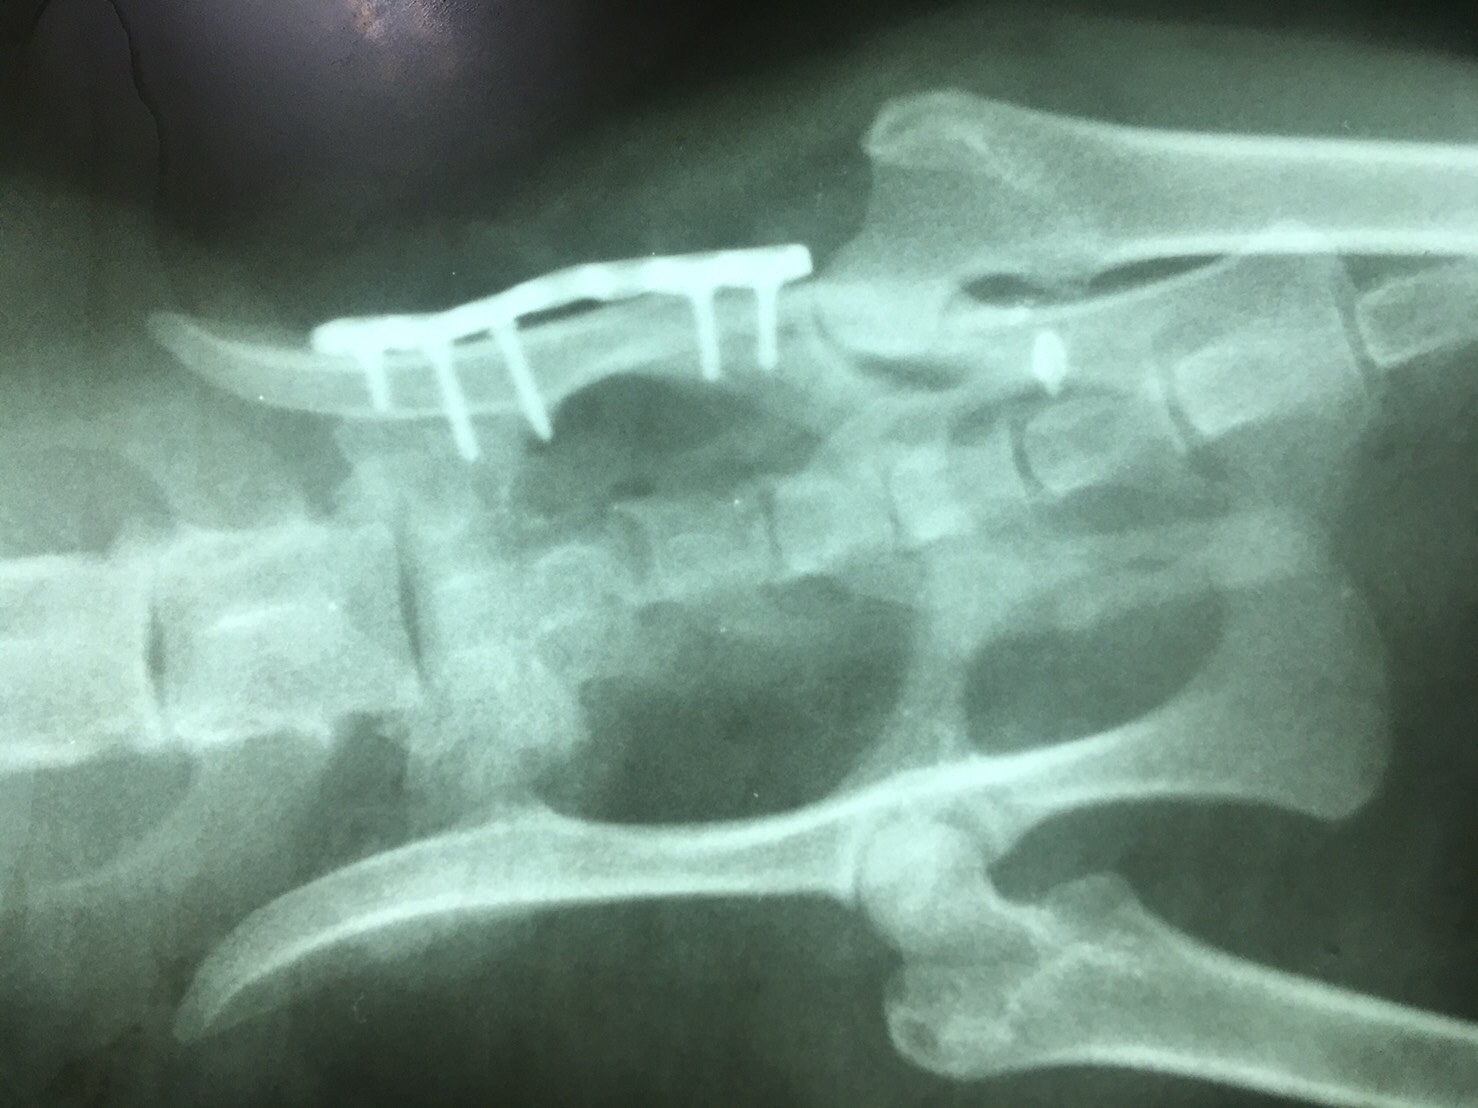

โรงพยาบาลสัตว์หมอพลอย ม.ฉัตรไพลิน